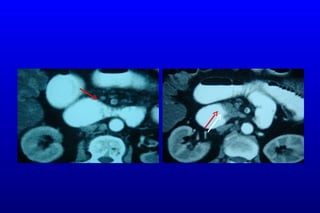

CTA: SMA Emboli

SMV Trombozu

Tanı Önceki yıllar:  klinik tanı, konvansiyonel anjiografi ,  DPL Günümüzde:  BT anjiografi,  Sensitivit e :  %  96 Multidetektör - multislice  Spe s i f i te : %   94 Avantajlar Vasküler anatomi Ayırt edici tan ı

BT Anjiografi: Multidete k t ö r  BT akut ve kronik mezenterik iskeminin tanısında idealdir   Horton KM, et al.  Radiol Clin North Am. 2007 Mar;45(2):275-88. Review